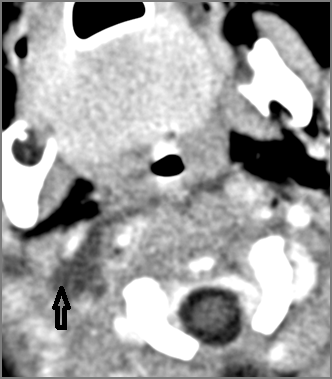

9 month old male presenting to the emergency room with poor feeding, fever, respiratory distress and possible retropharyngeal abscess or suppurative retropharyngeal adenitis.Exam

There is suppurative retropharyngeal lymphadenopathy. |

Yes | NA |

If there is suppurative retropharyngeal adenopathy what is the maximum short axis dimension of the largest suppurative node. Measurement |

< 2cm | NA |

There is edema/abscess within the adjacent parapharyngeal and retropharyngeal spaces. |

Pharyngitis with suppurative retropharyngeal adenitis.